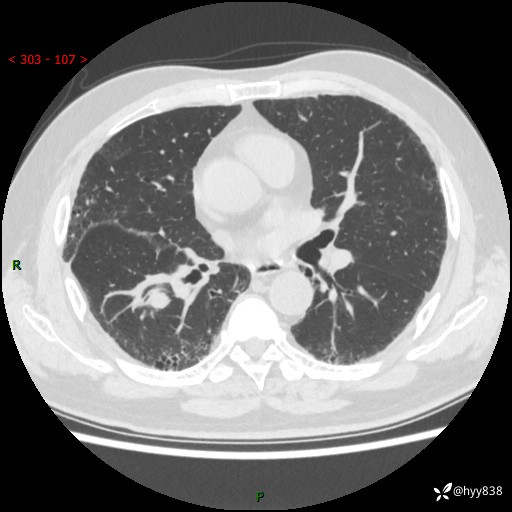

71岁/男,咳嗽伴气促半月。一年前肺手术史,又见两个结节,穿刺结果意外---结果公布~

【现病史】:患者半月前无明显诱因出现咳嗽、咳痰,为白色粘痰,无明显加重与缓解因素,伴气促,无发热,无大量脓痰,无胸痛、咯血,无哮鸣音,到我院就诊,胸部CT示右肺结节增大,并口服药物治疗无明显好转,具体用药不详,为求进一步治疗随来我院,经门诊以“孤立性肺结节”收入我科。 病程中患者精神、饮食可,睡眠不佳,大小便正常,体力下降,体重未见明显下降。

[既往史]:2022-06于当地第一人民医院确诊慢阻肺,现规律使用杰润(1次/日);2023-04-06于当地市第一人民医院行胸腔镜右肺上叶楔形切除术+右肺上叶切除术+淋巴结清扫术+胸膜黏连松解术,确诊为右肺鳞癌 pT2aN0M0 Ib期

【检查】:胸部CT平扫+增强